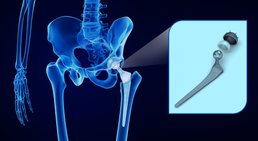

Hüftprothese

In der Ordination biete ich Patienten verschiedene konservative Behandlungsmaßnahmen, um Hüftarthrose zu behandeln, Schmerzen zu lindern,...

Gerne bespreche ich mit Ihnen die unterschiedlichen Behandlungsmaßnahmen bei Knie- oder Hüftbeschwerden (konservative Möglichkeiten, gelenkerhaltende Operationstechniken); sollte ein künstlicher Gelenkersatz erforderlich sein, biete ich im Bereich der Hüfte die minimal-invasive und im Bereich des Knies die computernavigierte Operationstechnik an. Darüber hinaus bin ich auf Wechseloperationen spezialisiert – Probleme mit bereits bestehenden Kunstgelenken werden von mir umfassend abgeklärt und behandelt, stets mit dem Ziel, dass meine Patienten ihre schmerzfreie Mobilität möglichst rasch wiedererlangen.